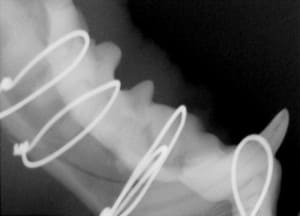

Repair of Maxillofacial Fracture

Pets can be involved in trauma that can cause fractures to their head, teeth, and jaw bones. Correctly repairing these fractures is extremely important for your pet to have normal function of their mouth. If a jaw fracture is allowed to heal in an abnormal position, your pet may have great difficulty chewing and can be in significant pain. Many fractures can be successfully treated with minimally invasive oral procedures, but more complicated cases may require bone plating techniques. The Center offers cone beam CT imaging which provides extremely detailed images of the bones of the head and skull. Advanced imaging with CBCT facilitates selection of the best surgical technique to get your pet back to eating and comfort as soon as possible.